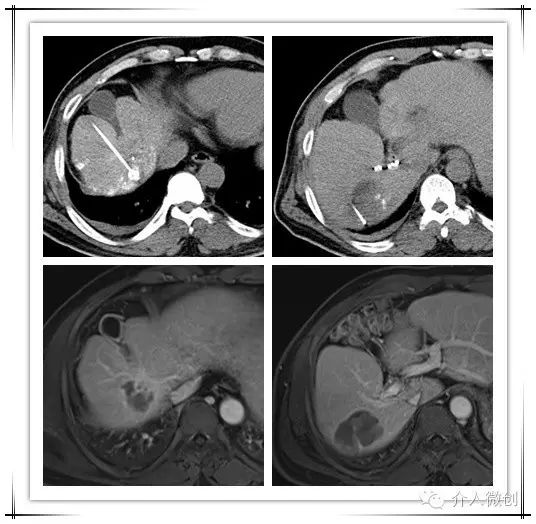

针对新情况,为该患者制定治疗计划:肝动脉化疗栓塞术+射频消融术控制肝内新发瘤灶,并联合碘125放射性粒子植入控制门脉右支癌栓。

DSA造影显示右肝膈顶可见新发病灶肿瘤染色

CT引导下肝癌射频消融术+门脉癌栓放射性粒子植入术,术后2周复查肝脏MRI提示肝内病灶得到有效控制,甲胎蛋白(AFP:14 ug/ml)亦明显下降,术后1个月甲胎蛋白降至正常范围(AFP:3.9 ug/ml)。

射频消融+放射性粒子植入